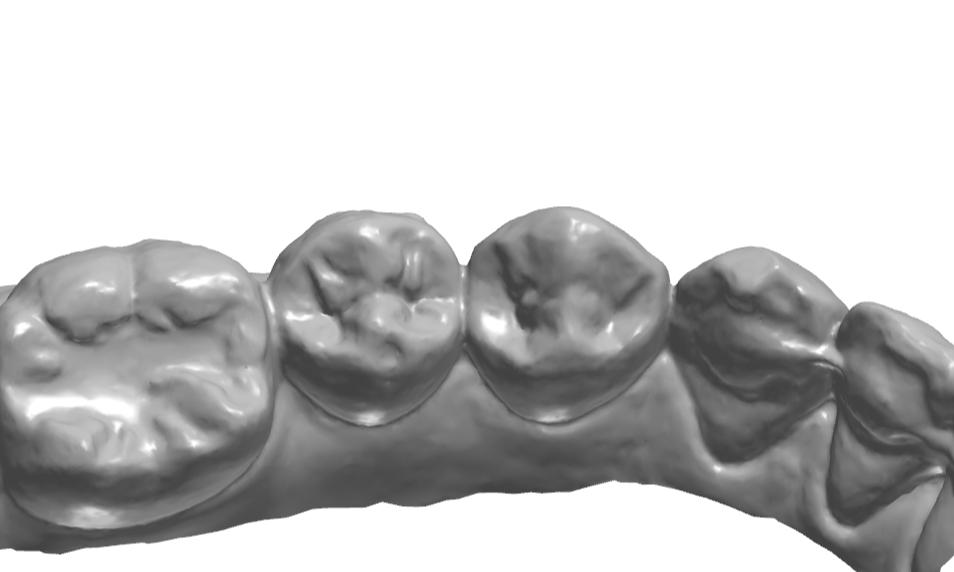

34번이나 35번을 생각보다 모양 잡기가 어려운것 같아 여러 방향에서의 모습을 찍어놓고

가끔식 보고자 하여 이렇게 기록으로 남겨본다.

교합면에 형성되어 있는 엠브레져 체크.

교합면 확대.